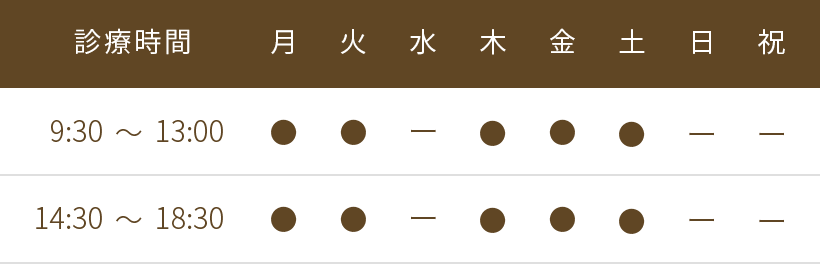

治療前

前歯2本がハの字形に外開きとなっており、やや前方にも飛び出して出っ歯のような状態でした。

セラミック矯正において

別症例にはなりますが、通常、歯のセラミック治療の際は上記の写真のように歯を削って筒状に形を整えて、セラミックを被せます。神経が生きている歯であれば、極力神経は取らない方が良いと思います。 神経を取ってしまうと、歯の強度が落ち、根が膿んでしまう原因にもなり、歯の寿命が短くなってしまいます。しかしセラミック矯正は、セラミックで歯並びを整える治療になるので、度々歯の神経が治療の妨げになるため、取られることがあります。

歯の内部には、神経が入ってる空洞があり、歯を削る際に、この神経が邪魔をしてしまいます。歯並びが、悪ければ悪いほど、歯を削る量が多くなり、神経を取らなければならない可能性は高くなります。よって歯の神経を温存しながら、セラミック矯正を行う際は、限界があることを理解しておかなければなりません。

当院では、神経を取るセラミック治療は行なっておりません。

治療途中1

上記写真は、神経に負担にならないように、数回に分けて、歯を削っていった状態です。

ピンクスポット

歯の内部には、歯の神経と共に血管があるため、歯を削って、神経近くになっていくと、内部の血管が見え始め、ピンク色や赤紫色のような色味になってきます。これをピンクスポットと言います。これ以上歯を削ると、神経がむき出しになり、神経を取らなければならなくなるため、神経を残すのであれば、これが削る限界となります。

治療途中2

上記写真は、歯を削る前と後の状態を重ね合わせたお写真になります。この患者さまの歯は、ハの字型のように外側に傾いていたため外側の部分がより削る量が多くなり、ピンクスポットが外側に認められるようになりました。緑の矢印部分で、外側の方が、削られている量が多いのが分かります。

治療後

最終のセラミックの被せ物が入った状態です。以前のハの字形は無くなり、綺麗な歯並びとなりました。隣の天然の歯とも見分けが付かないよう、自然な感じに仕上げることができました。

患者さまも、「本当に綺麗にありがとうございました✨」「職場でもよく褒められます」と大変喜んで頂きました。

治療前後比較(口腔内)

神経を抜かないセラミック矯正は、意外にも適応される症例は少なく、軽度の症例に限ります。これ以上の歯並びの不正は、神経を取る治療が必ず必要になります。

治療前後比較(口元)

近年では、セラミック矯正で、劇的な変化を謳う症例も多く見かけますが、その反面、歯の寿命や膿んだりするトラブルなど様々なリスクがあることを十分認識する必要があります。当院には、そのようなセラミック矯正でトラブルに見舞われたご相談をたくさん頂きます。皆様、口を揃えて仰られるのが後悔の念です。そうならないためにも、セラミック矯正を受けられる際は、リスクなど十分に理解し、慎重に検討することが重要です。